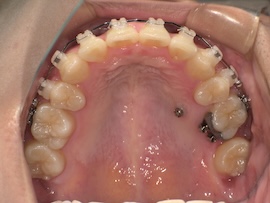

そして1ヶ月後、

左上の親知らずとその手前の歯の間に隙間があり、今は食事のたびにものが詰まります。

その隙間を閉じつつ左側の噛み合わせをより良くするため、再度ゴムかけをすることになりました。

写真にはないですが今回は左上の3番目(犬歯)と左下の7番目(一番奥)にゴムをかけます。以前左下は6番目でゴムかけをしていたのでさらにかけるのが難しくなりましたが、それでもやはりすぐに慣れるものです。

あとは正中(上下の前歯の真ん中)が合うようにも、最後のゴムかけをあと数ヶ月頑張ろうと思います。